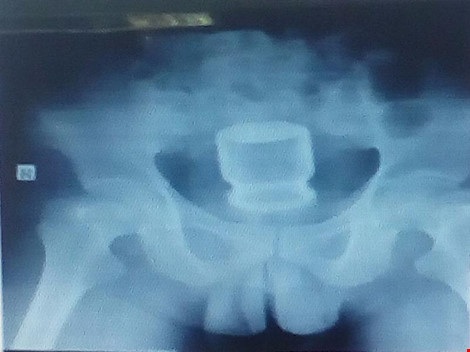

Kết quả nội soi trực tràng và X-quang cho thấy lọ thủy tinh khá to còn nguyên nắp đậy, bên trong chứa đầy nước yến. Do không thể dùng kỹ thuật nội soi để lấy lọ nước yến khỏi người ông L. nên các BS phải phẫu thuật cấp cứu.